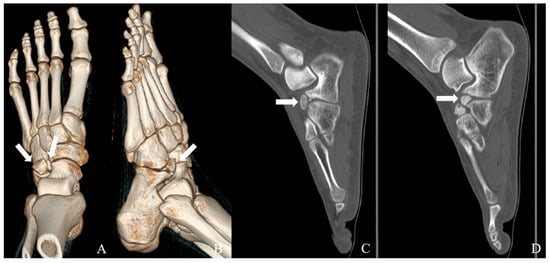

Multiple Calcaneus Secundarius Ossicles Presenting with Anterior Foot Pain: A Case Report Highlighting Characteristic Imaging Features

by Ki Jin Jung, Eui Dong Yeo, Jeong Han Nam and Woo Jong Kim

Background: Calcaneus secundarius (CS) is an accessory ossicle located at the anterior aspect of the calcaneus and is typically an incidental and asymptomatic radiographic finding. However, it may become symptomatic following trauma or repetitive mechanical stress and can mimic anterior calcaneal process [...] Read more.

Background: Calcaneus secundarius (CS) is an accessory ossicle located at the anterior aspect of the calcaneus and is typically an incidental and asymptomatic radiographic finding. However, it may become symptomatic following trauma or repetitive mechanical stress and can mimic anterior calcaneal process fracture or tarsal coalition, leading to diagnostic confusion. The presence of multiple independent CS ossicles represents a rare morphological variant and a potential source of diagnostic ambiguity. Methods: We report the case of a 19-year-old male soldier who presented with progressive anterior foot pain following soccer activity without a clearly identifiable traumatic event. Radiographs, computed tomography (CT), and magnetic resonance imaging (MRI) were performed to evaluate the underlying pathology. Results: CT demonstrated two separate, well-corticated accessory ossicles adjacent to the anterior calcaneal process without bony continuity. MRI revealed focal bone marrow edema (BME) at the calcaneus–ossicle interface, suggesting mechanical irritation at the fibrous connection. Due to persistent symptoms and concordant imaging findings, surgical excision was performed, resulting in immediate pain relief and return to full daily and sports activities without recurrence at the 1-year follow-up. Conclusions: Multiple CS ossicles may produce fragment-like imaging appearances and increase the risk of misdiagnosis. Recognition of characteristic imaging features, particularly well-corticated ossicles and focal BME at the ossicle–calcaneus interface, together with clinical correlation, is essential for accurate diagnosis and appropriate management in patients with persistent anterior foot pain. Full article

Figure 1